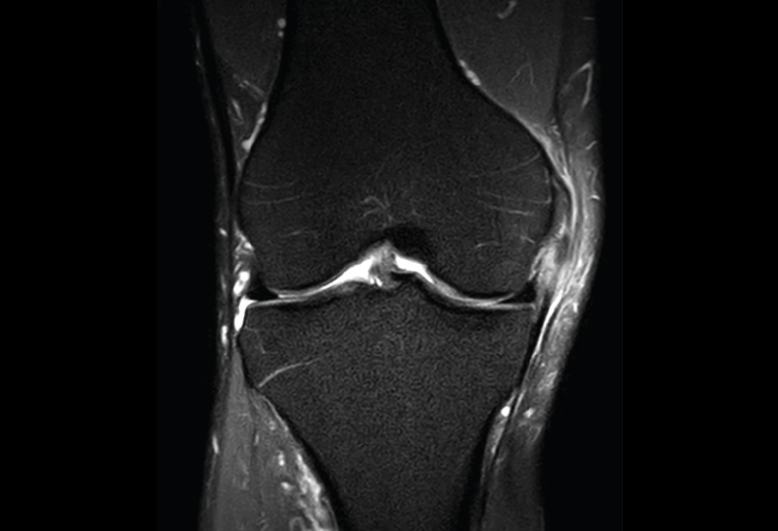

Se visualizan como estructuras lineales hipointensas en todas las secuencias.

1.2.1. Ligamentos laterales

Figura 36. Corte de secuencia coronal T2 Fat-Sat: ligamentos colaterales normales.

Ligamento lateral interno (LLI) y ligamento lateral externo (LLE) (Figuras 36, 37, 38 y 39).